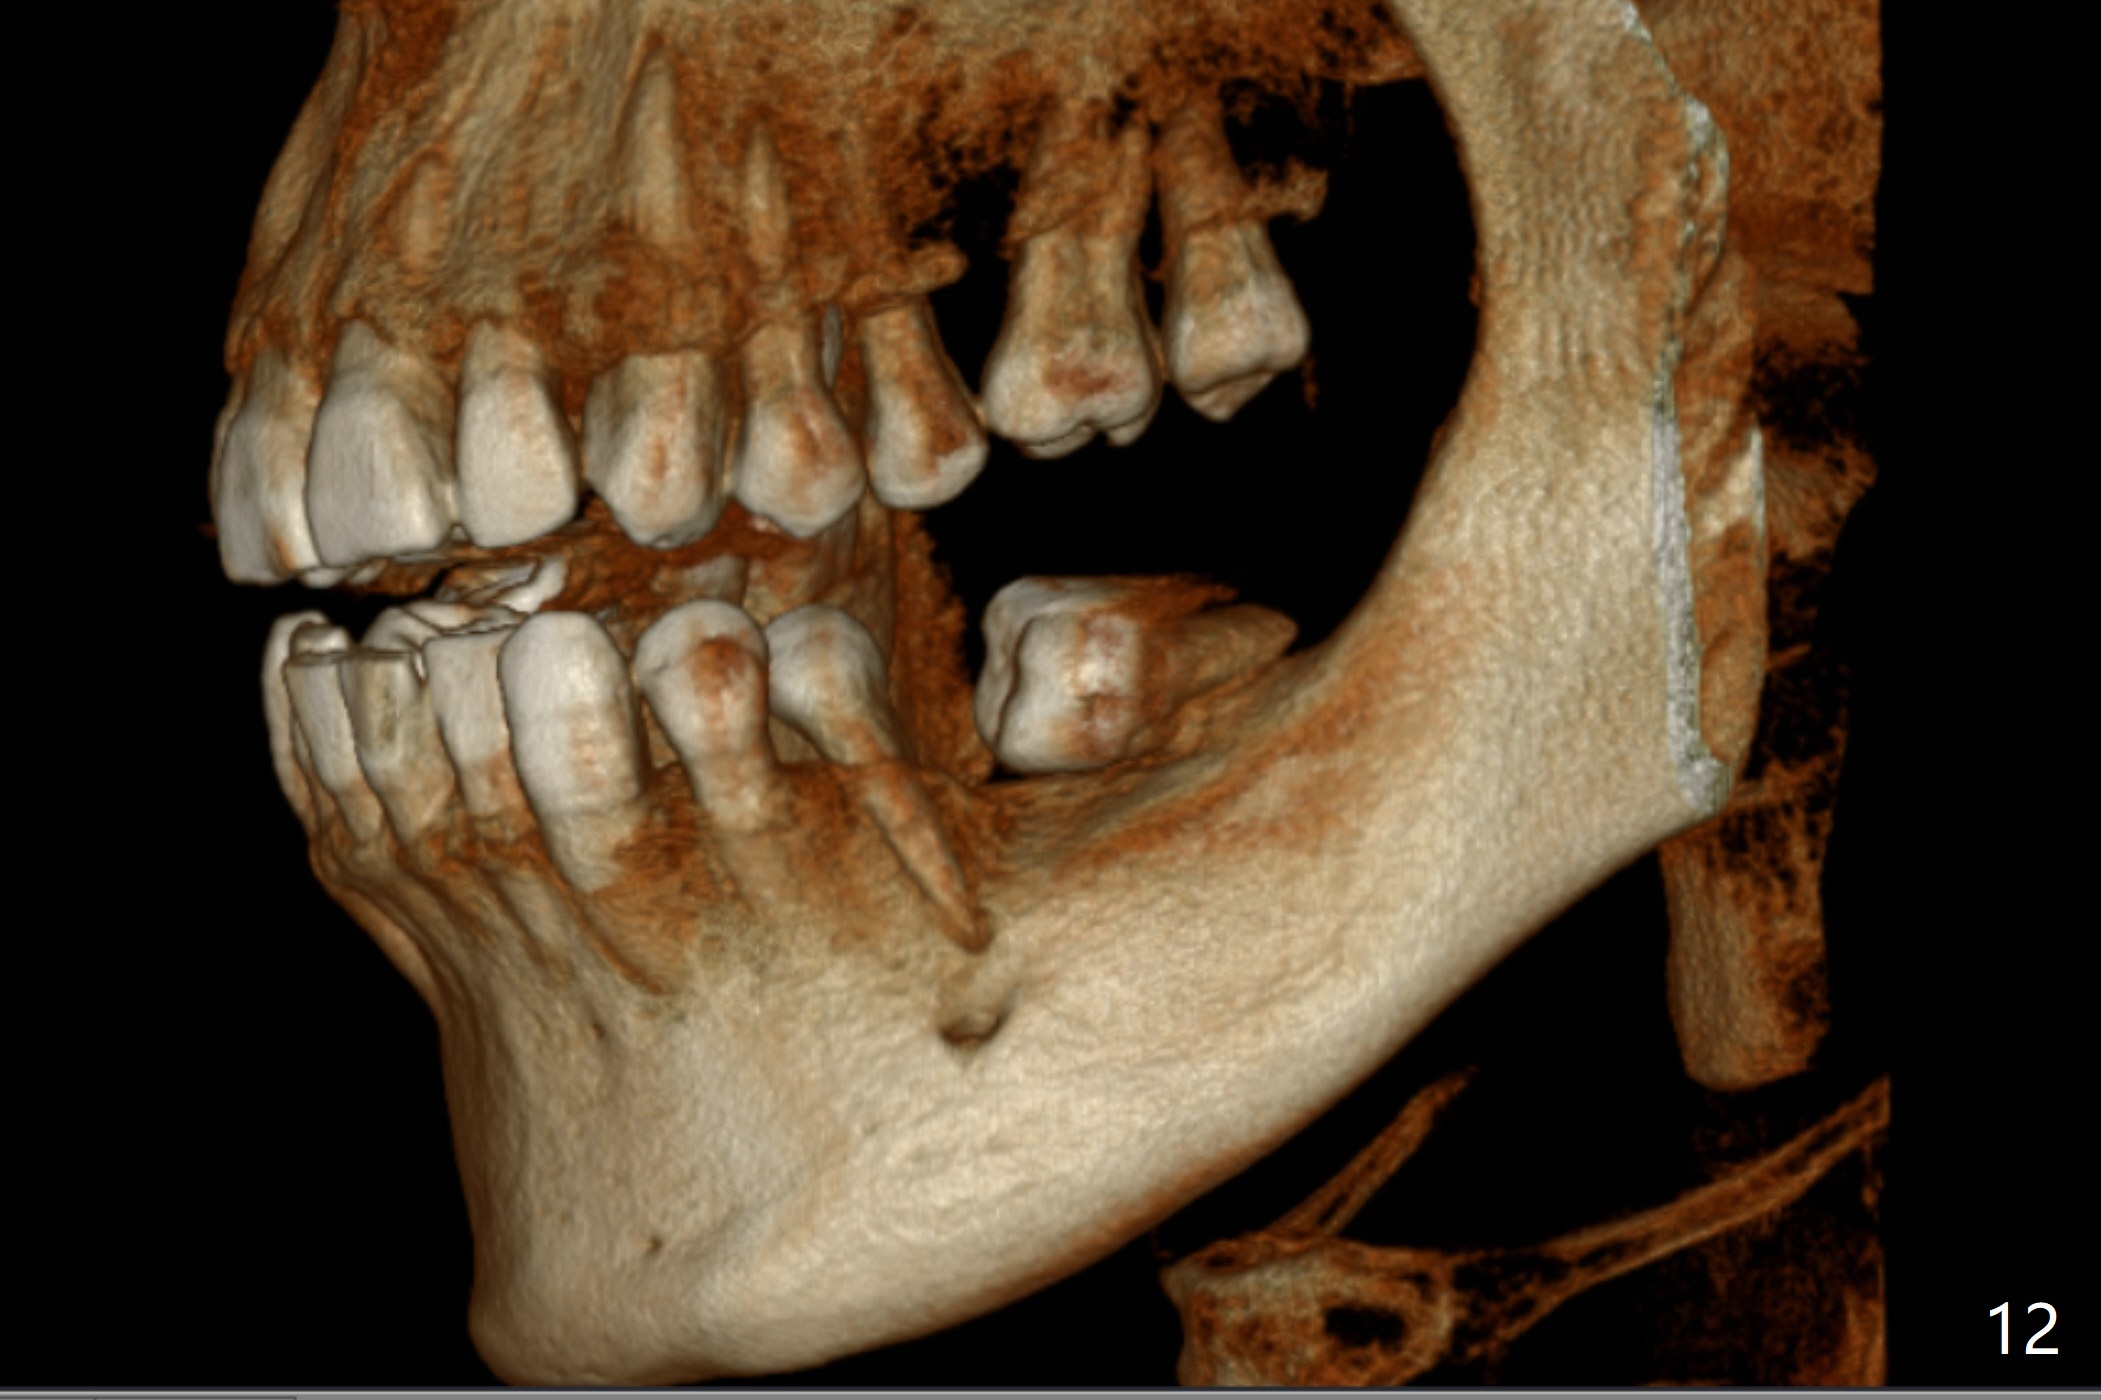

A 43-year-old man has poor dentition on the left: 1st molar missing, 2nd molar mesial inclination (Fig.1) and 2nd bicuspid lingual tilt (Fig.2). The latter is nonfunctional (Fig.3 (linguoposterior view). Two molar implants will be placed in a position so that their crowns will be in cross bite (Fig.4,5), the same occlusal scheme as the teeth #21 and 22. When these implants osteointegrate, the provisional crowns (Fig.6 P) will be supraocclusal so that there is clearance (*) for #20 to upright orthodontically (Fig.7-9). Moreover, these implants will be used anchorage as well as #21 and 22. Panoramic X-ray (Fig.1) and CBCT (Fig.10-12) show limited bone height at the sites of #18 and 19. It appears that 5x8 and 5.9x6 mm implants are appropriate with ridge reduction at #19.